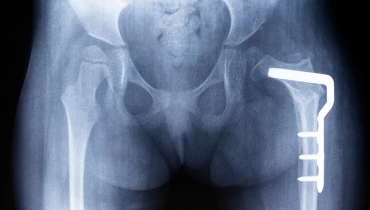

Остеосинтез бедренной кости – это хирургический способ вернуть сломанной кости правильную ось, длину и стабильность, чтобы человек снова ходил без боли и страха опоры. Суть метода: точная репозиция отломков, затем надежная фиксация специальной конструкцией – пластиной, штифтом, винтами или стержнем. Такая операция уменьшает риск укорочения и деформации, позволяет ранние движения и ускоряет восстановление, потому что костный каркас получает условия для срастания без «ступеньки» и смещения. Когда анатомия восстановлена, бедренный сустав работает как единый механизм, а реабилитация идет по понятному плану.

• Накостный. Пластина ложится на кость как «мост», удерживая фрагменты и позволяя точечную компрессию по линии. Остеосинтез бедренной кости пластиной незаменим в метафизе и у суставных краев, где критична геометрия. Угловая стабильность винтов помогает сохранять высоту и форму без избыточного пережатия. Такой способ уместен, когда нужен доступ для прямой репозиции и контроля рельефа.

Фиксация